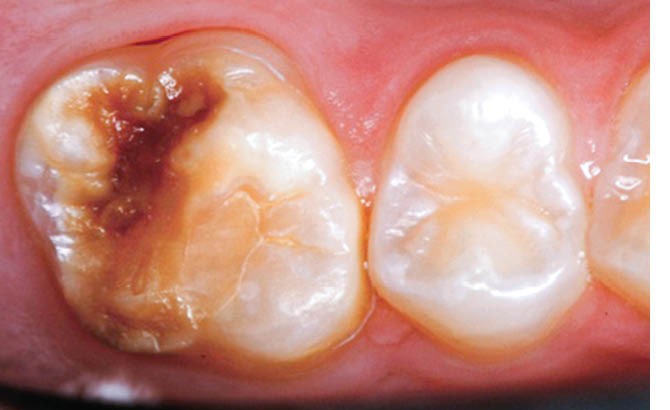

L’émail dentaire, tissu le plus dur et le plus minéralisé du corps humain, peut être affecté par des anomalies génétiques inscrites dans le génome de l’individu, mais également par des facteurs environnementaux. Ces facteurs sont multiples et signent un événement ou une exposition à un xénobiotique au cours de la vie de l’individu. Parmi les atteintes développementales acquises de l’émail, outre la fluorose, figurent les hypominéralisations à type de MIH (Molar Incisor Hypomineralization). Celles-ci sont observées de manière caractéristique sur une ou plusieurs premières molaires permanentes et potentiellement les incisives permanentes éruptant vers l’âge de 6 à 7 ans d’après la description qui en a été faite en 2001 [3] (fig. 1 à 3). La prévalence est importante, la MIH touchant, selon les méta-analyses les plus récentes, plus de 13 % des individus dans le monde, et peut varier selon les études et les pays dans lesquels elles sont menées [4, 5]. Son étiologie est encore incertaine, mais la communauté scientifique s’accorde sur le fait qu’elle serait multifactorielle et notamment en lien avec la survenue d’une hypoxie à la naissance, de fortes fièvres, des épisodes infectieux de la sphère ORL dans la petite enfance ou encore avec une prédisposition génétique [6]. Cette pathologie aurait toujours existé, mais sa prévalence semble être en nette augmentation. Peu d’études ont été réalisées sur cette évolution dans le temps [7].

Les cellules responsables de la synthèse de l’émail, les améloblastes, disparaissant au moment de l’éruption des dents, les défauts de structure et de qualité de l’émail sont irréversibles. L’émail dentaire est ainsi capable d’enregistrer des événements environnementaux ayant eu lieu lors de sa formation. Ces défauts sont donc en quelque sorte le disque dur des contaminations que les améloblastes ont subies. De ce fait, le défaut de minéralisation caractérisant le MIH est le signe d’une exposition environnementale délétère intervenue au cours de la période périnatale (période d’amélogenèse des dents impactées par le MIH), soit environ 5 ans avant leur éruption (fig. 4).

Les résultats de ces études suggèrent l’implication de perturbateurs endocriniens dans l’hypominéralisation de l’émail et dans la MIH. Le DEHP, à l’instar du bisphénol A, pourrait contribuer au développement de cette pathologie. Les dents atteintes signeraient une exposition précoce à ce polluant.